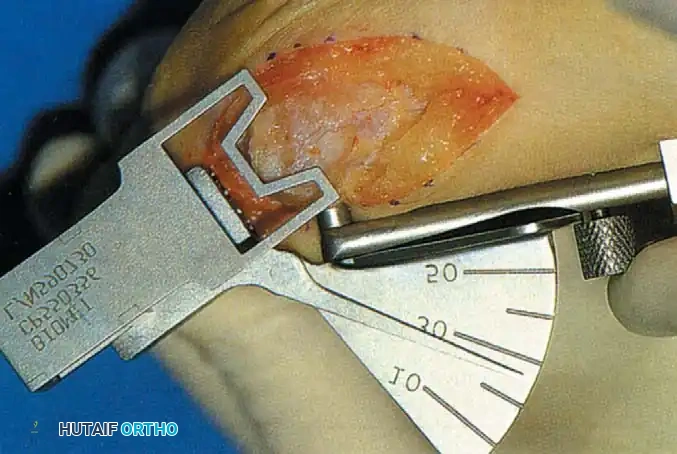

Fig. 78-8 A, Determination of position of articular surface of metatarsal head in relation to longitudinal axis of fi rst metatarsal. B, Measurement of distal metatarsal articular angle at time of surgery. Markings are at medial and lateral margins of articular surface of fi rst metatarsal head and longitudinal axis of fi rst metatarsal shaft. metatarseum between the bases of the fi rst and second metatarsals might preclude the effectiveness of a soft-tissue procedure alone to provide suffi cient correction of the increased intermetatarsal angle. Likewise, accessory sesamoids and prominent ungual tuberosities at the interphalangeal joint contribute to a painful callus at the tibial side of this joint. An os tibialis externum frequently is associated with excessive hallux valgus interphalangeus. Varus of the fi rst metatarsal might be a signifi cant part of the overall deformity of the foot even with an intermetatarsal angle of less than 10 degrees. Metatarsus varus with a relatively small hallux valgus angle (15 to 20 degrees) may produce signifi cant deformity even though the angles are not excessive. The usefulness of computer-assisted compared with manual measurement of the intermetatarsal angle, hallux valgus angle, and distal metatarsal articular angle is still uncertain. Both methods have closer interobserver and intraobserver correlation in measurement of the intermetatarsal angle and hallux valgus angle than in measurement of the distal metatarsal articular angle. The reliability of either method has such a wide range (5 degrees), however, that measurements of these angles, although useful as a guide, do not provide a completely reliable indication of the magnitude of deformity. Condon et al. suggested that the reliability of the intermetatarsal angle can be improved by careful technique and by making the measurements at least twice and averaging them. Schneider et al. reported two methods of determining angular measurements based on distinctly different reference points: (1) a longitudinal axis of the fi rst metatarsal using middiaphyseal reference points, and (2) a center-head technique using a center head (center of the articular surface) and center base